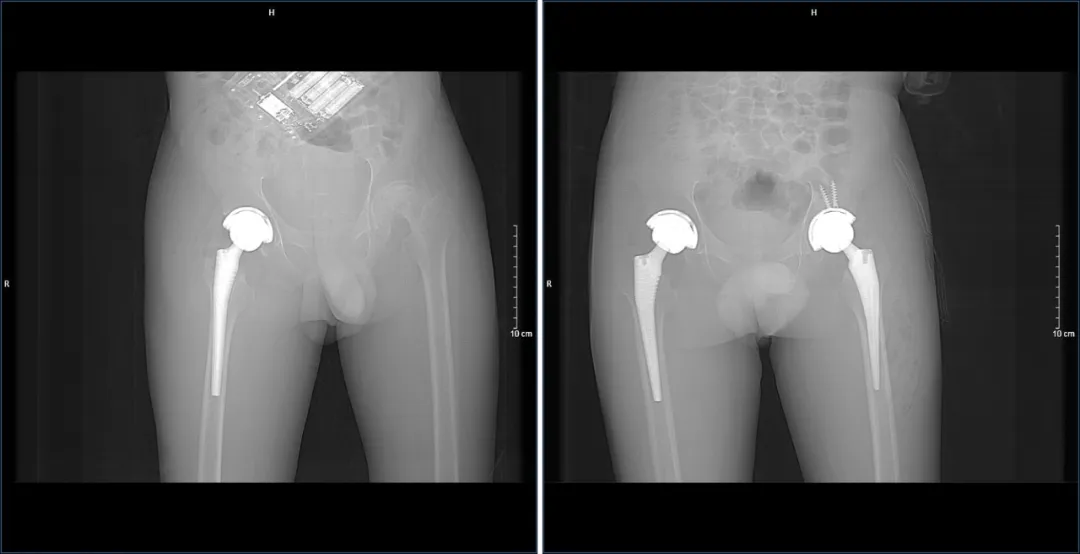

据了解,患者因长期饱受“双侧股骨头坏死”的折磨,生活受到了严重影响。在多方求医无果后,他们最终选择来到济南南郊医院,找到了杨学良主任团队。面对患者的复杂病情,杨学良主任没有丝毫犹豫,立即组织团队进行了深入的病例研讨。结合医学影像及一系列完善的检查,团队为患者量身定制了一套分阶段髋关节置换术的手术方案。

手术方案决定先为患者进行右侧髋关节置换手术,待术后恢复良好,再进行左侧髋节置换手术。这一决策不仅体现了杨学良主任团队的专业素养,更彰显了他们对患者生命的尊重和负责。手术过程中,杨学良主任凭借精湛的医术和丰富的经验,带领团队顺利完成了手术。术后,患者在医护人员的精心照料下,恢复迅速,经过复查,各项指标均符合预期手术目标,生活质量得到了极大改善。